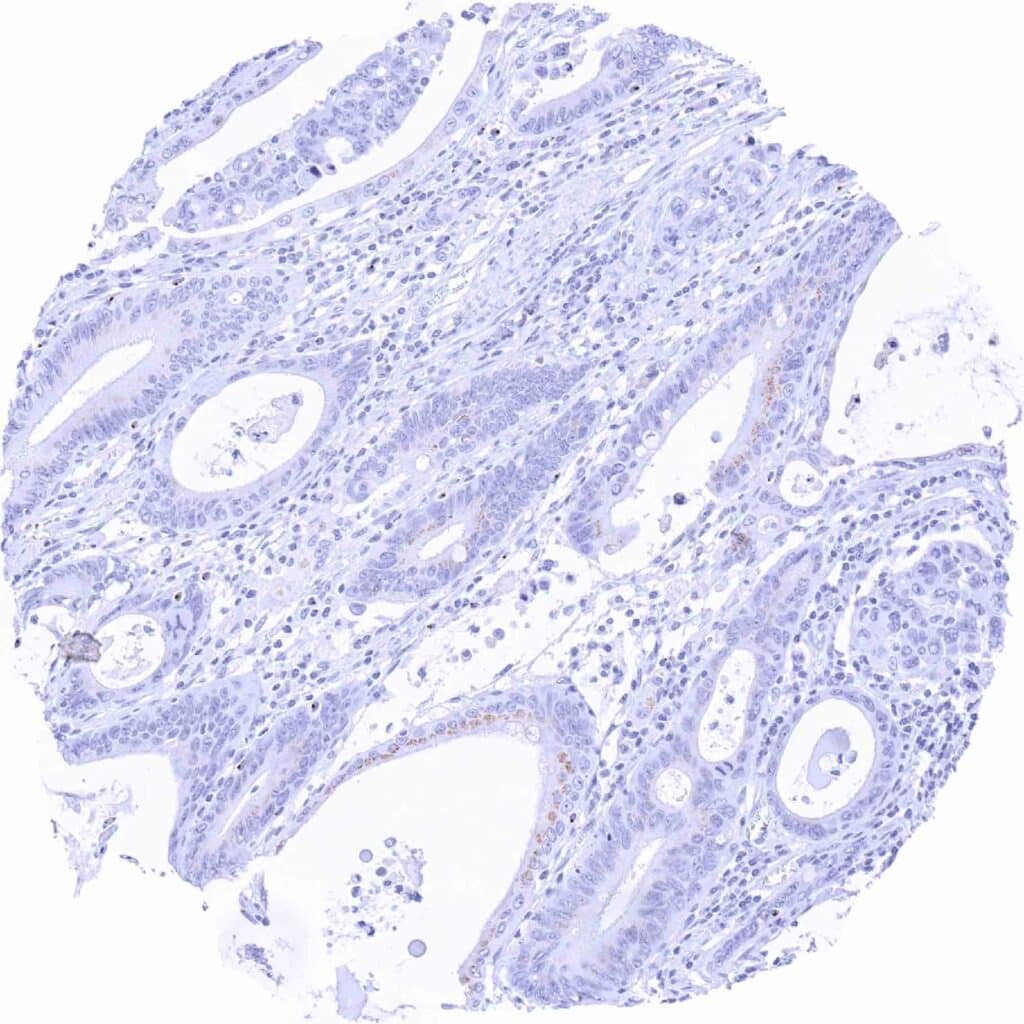

Esophagus – Adenocarcinoma showing weak, granular perinuclear Prostein staining of a fraction of tumor cells

Stomach – Gastric adenocarcinoma showing weak granular perinuclear Prostein staining of most tumor cells